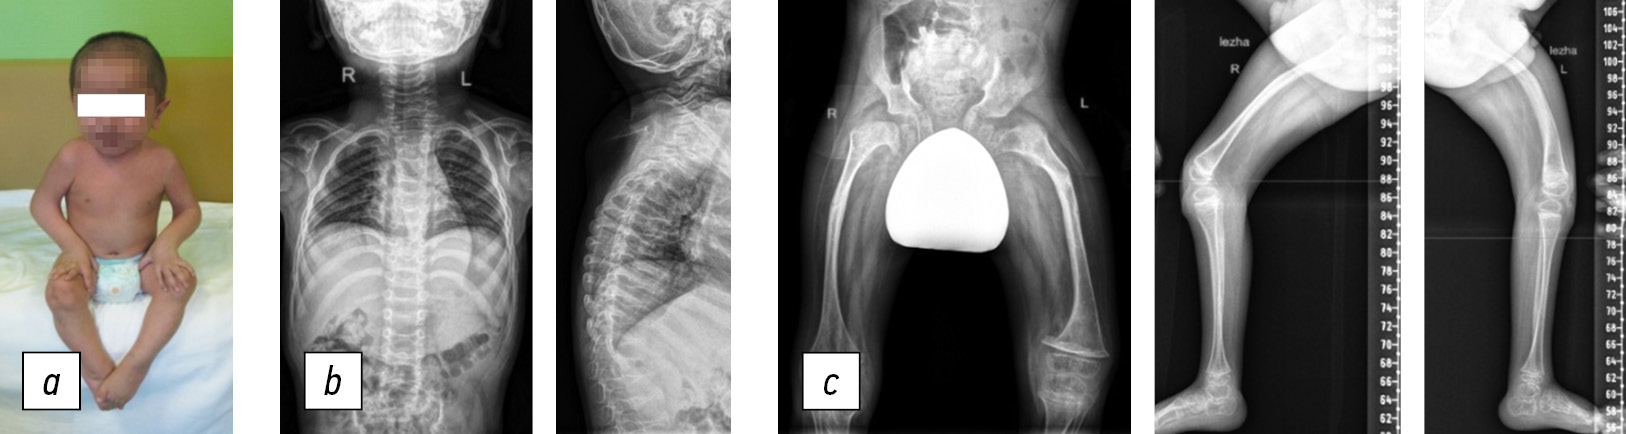

Fig. 1. Patient H, eight years old, Bruck syndrome, type 2: a, general view of the patient (does not walk); b, spine radiographs in anteroposterior and lateral projections: 10° frontal deviation of the spinal axis, wedge-shaped vertebrae; c, panoramic radiograph of the lower extremities in anteroposterior projection, varus-antecurvation deformity of the femurs; d, radiograph of the femurs in anteroposterior projection, intramedullary fixation with a telescopic rod

Patient H, delivered independently during the second term of her mother’s second pregnancy, had a birth weight of 3900 g and a height of 52 cm. No orthopedic pathology was detected. Since birth, patient H has been under the supervision of a neurologist because of birth trauma to the central nervous system. At age 1, patient H stopped standing and making attempts to walk. At age 3, the patient experienced a left femur fracture for the first time. Compression fractures of the ThXII–LI vertebrae were detected when she was 4 years old. She suffered three fractures of the right and left femur between the ages of six and eight. At age 6, examination showed a decrease in skeletal bone mineral density. Bisphosphonates were administered twice a year to treat osteoporosis, which helped reduce fractures. At age 8, corrective osteotomy of the right and left femur was performed for the first time, with fixation using a telescopic rod (Fig. 1). Standard consolidation periods followed osteotomy.